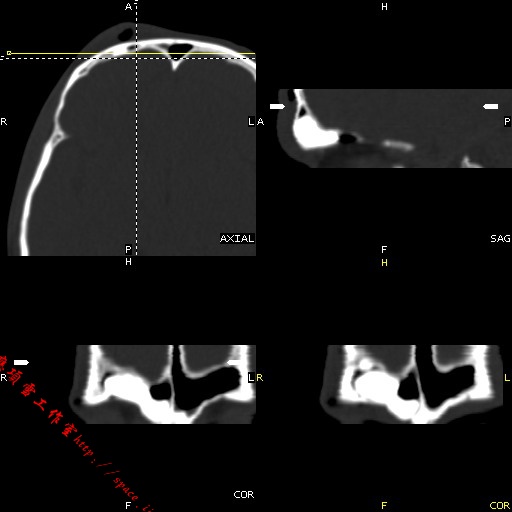

m49y外伤常规ct发现筛额窦右侧高密度块影 。

右侧额筛都内致密性高密度影,余骨皮质未见明显异常改变,右额皮下血肿伴少许积气,我想是致密影是骨瘤.

右侧额筛都内致密性高密度影,境界清楚,余骨皮质未见明显异常改变,符合骨瘤表现

右侧额筛都内致密性高密度影,境界清楚,余骨皮质未见明显异常改变,考虑额筛窦内生性骨瘤.

颅面部骨瘤一般密度致密,多发额骨及鼻窦腔壁,呈扁丘样改变.边界清楚,大部分密度均一.

此片应与验证纤维化做一区分

1、致密型骨瘤。2、右额部头皮挫裂伤。

右额窦至密性骨瘤,右额骨皮下软组织挫伤拌积气.